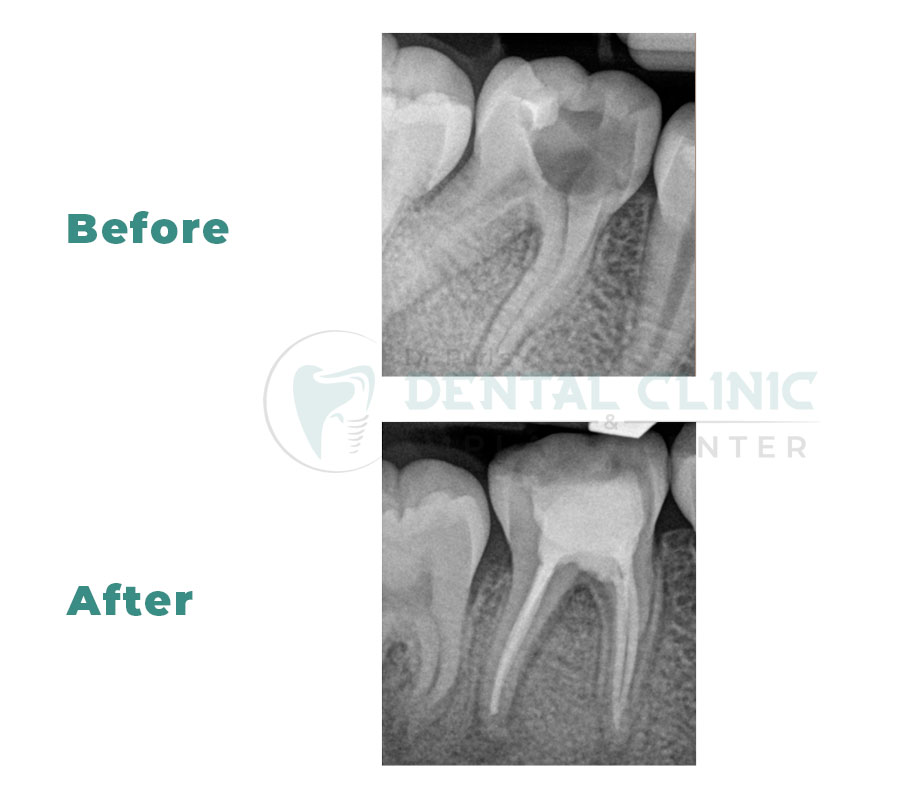

Root canal treatment (RCT) is designed to eliminate bacteria from the infected root canal, prevent reinfection of the tooth and save the natural tooth. When one undergoes a root canal, the inflamed or infected pulp is removed and the inside of the tooth is carefully cleaned and disinfected, then filled and sealed.

After RCT , the tooth is restored with a crown or filling for protection and will continue to function like any other tooth.